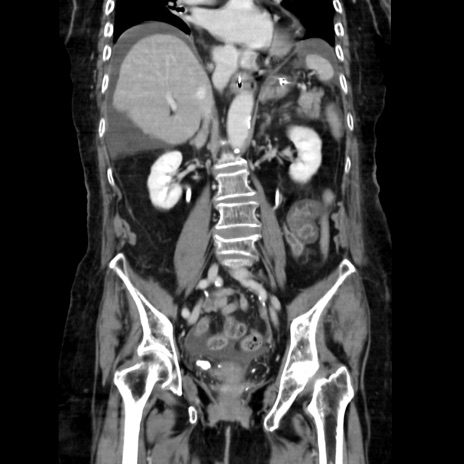

症例40(冠状断像)

【症例】90歳代女性

【主訴】腹痛・嘔吐

【現病歴】 食欲低下、嘔吐があり昨日他院受診。肺炎と診断され入院となる。入院後より腹部全体に圧痛あり。胃管留置され経過みていたが、症状持続するため、

当院転院となる。

【既往歴】胸椎圧迫骨折、胆石症

【身体所見】腹部:中央に激痛あり、圧痛あり、反跳痛不明

【データ】WBC 17100、CRP 18.82

冠状断像